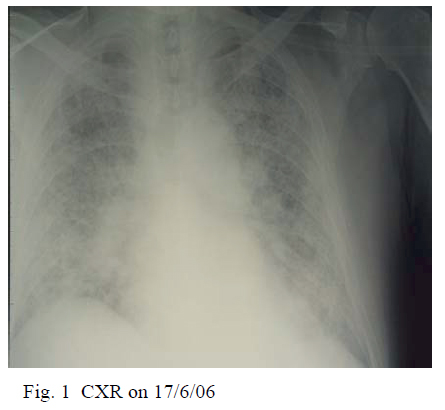

Chest radiography (CXR) on admission showed bilateral diffuse ground glass opacity and reticulonodular shadowing bilaterally (Fig. 1). Electrocardiogram was normal. Echocardiogram demonstrated normal left ventricular ejection fraction 76.8 % and normal left ventricular size. No other abnormalities were identified.